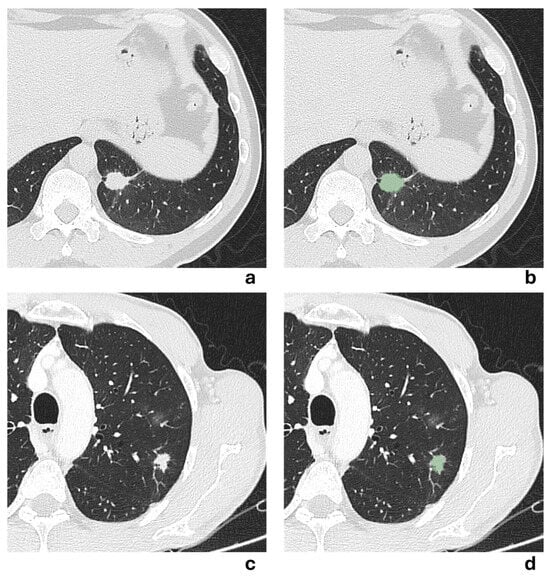

Two representative NSCLCS cases with a tumor major axis < 3 cm are illustrated in Figure 5. In the first case (a,b), the presence of a pleural tag suggested a radiological suspicion of pleural invasion, but it was not confirmed by histological examination. In the second case (c,d), no radiological suspicion of pleural invasion was raised due to the absence of a pleural tag, but histological examination revealed pleural invasion. All models failed to correctly predict the presence of pleural invasion, except for the 3 mm-peritumoral radiomic model.

Figure 5. (a,b) Axial chest CT scan in lung window of a 54-year-old man showing a solid irregular nodule in the anteromedial basal segment of the left lower lobe, with evidence of a pleural tag sign, measuring 14.4 mm in major axis. The corresponding segmented lesion is shown in (b). Despite radiological suspicion, histological examination revealed no pleural invasion. (c,d) Axial chest CT scan in lung window of a 65-year-old man showing a solid irregular nodule in the apical segment of the left lower lobe, without evidence of pleural tag sign, measuring 22.3 mm in major axis. The corresponding segmented lesion is shown in (d). Histological examination revealed pleural invasion, despite no radiological evidence being suspected.